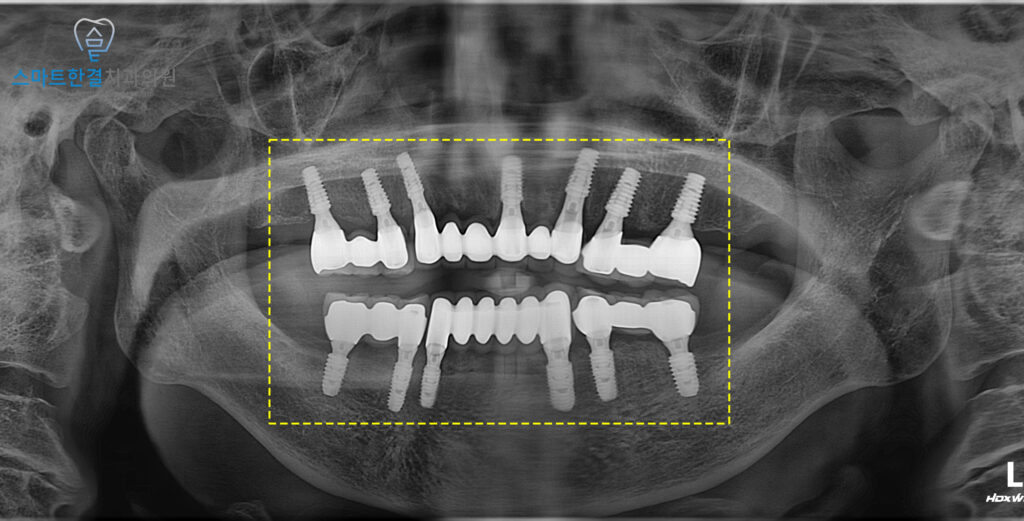

먼저 아래쪽 치아 발치 후

임플란트 식립을 진행했어요.

상실된 어금니 부위까지

빠짐없이 식립 해 저작력을

고르게 분산할 수 있도록 계획했으며,

단순히 치아 개수만 채우는 것이 아니라

교합 균형과 향후 보철의 안정성까지 고려해

위치와 각도를 세심하게 조정했어요.

식립 후에는 충분한 치유 기간을 거치며

임플란트가 잇몸뼈와 안정적으로

결합될 수 있도록 관리했는데요.

이 과정에서 정기적인 경과 관찰을 통해

염증이나 흔들림 여부를 꼼꼼히 확인했고,

잇몸 상태와 전반적인 구강 위생 관리도

함께 지도해 드렸답니다.

이후 임플란트가 특별한 이상 없이 잘 치유되어

맞춤형 지대주와 최종 보철 제작 후

형태와 색상, 교합 조화를 세심하게 확인한 뒤

영구접착해 드렸어요(^^)

이후 처음부터 안 좋았던 위 치아들도

치료를 희망하셔서

정밀 진단과 상담을 거쳐

전체 발치 후 임플란트 치료를

진행하기로 결정했어요.

위 임플란트 역시 식립 후

동일하게 충분한 치유 기간을 거치며,

결합되는 과정을 지켜보았어요.

이 기간 동안 정기적인 내원과

경과 관찰을 통해

잇몸 상태와 고정력을 확인하며,

이후 보철 단계로 안정적으로

넘어갈 수 있도록 관리 했어요.

아래 보철에 맞춰 위쪽 역시

형태와 교합을 세심하게 조정하여 제작하였으며,

위,아래가 조화롭게 맞물리도록

교합 균형을 중점적으로 확인했어요.

이를 통해 씹을 때의 불편함을 줄이고,

전체 임플란트를 보다 안정적으로

오래 사용하실 수 있도록 마무리했어요.^^